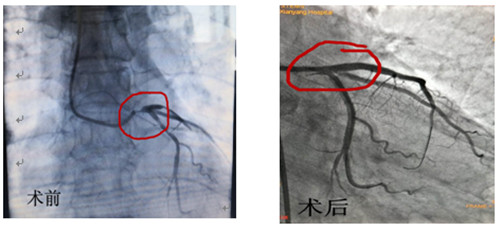

術(shù)前術(shù)后造影對比

12月16日早上8點30分手術(shù)如期進行,術(shù)前IVUS評估:左主干自口部至末端彌漫狹窄,最小管腔面積<1mm2,斑塊負荷程度>90%,主要為纖維脂質(zhì)斑塊,無明顯鈣化,回旋支開口尚可,前降支近段主要為纖維脂質(zhì)斑塊,亦無明顯鈣化。據(jù)此,手術(shù)方案定為:前降支近段至左主干口部串聯(lián)植入2枚支架,回旋支近段1枚支架,無需旋磨、切割,支架植入后IVUS評估:支架膨脹、貼壁良好,左主干口部支架梁覆蓋完全,手術(shù)完美收官。此系心內(nèi)二病區(qū)左梅主任及其團隊在導(dǎo)管室配合下完成的我院首例自主IVUS指導(dǎo)下左主干PCI。